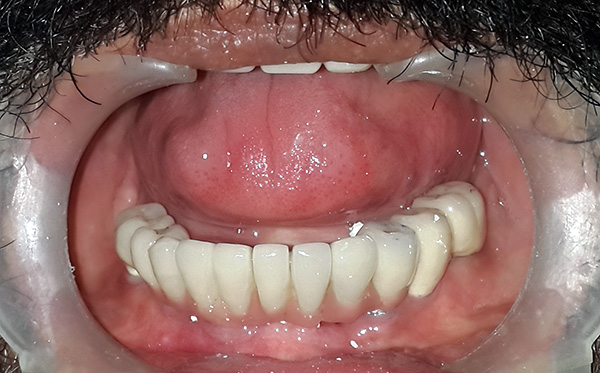

A foto abaixo mostra os implantes removidos da mandíbula: